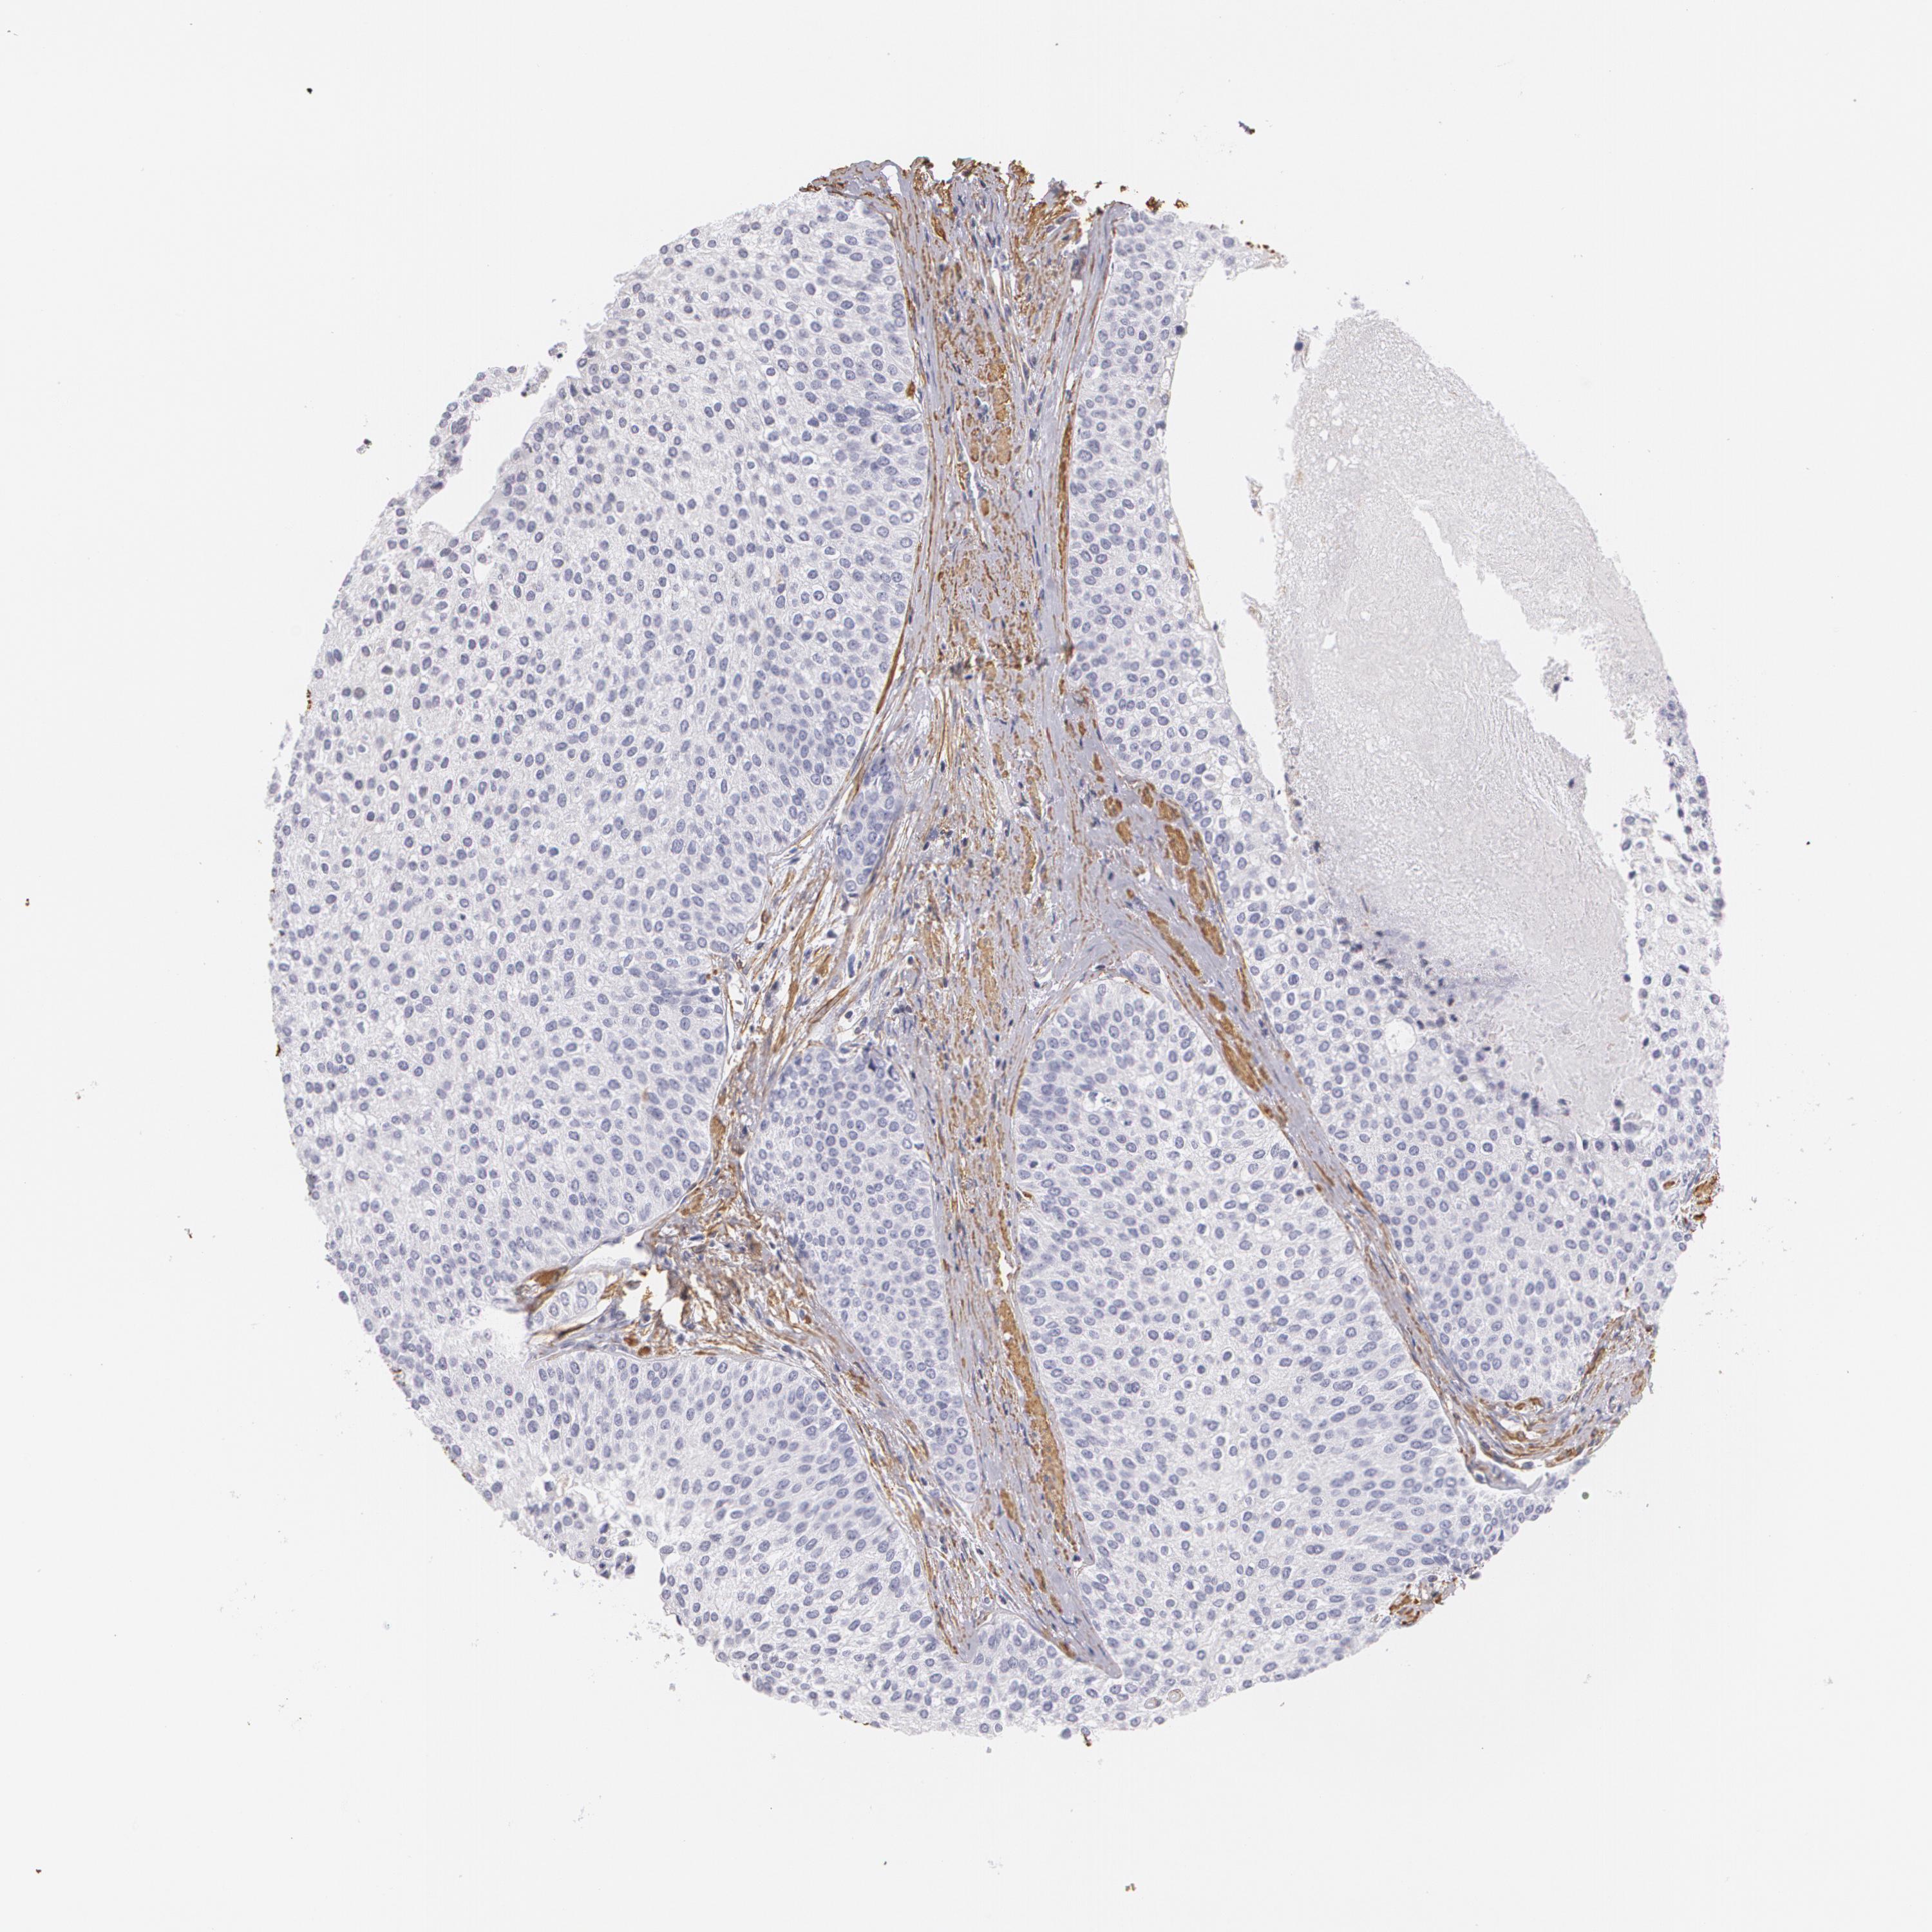

UROTHELIAL CANCER - Protein expressioni

A mouse-over function shows sample information and annotation data. Click on an image to view it in a full screen mode. Samples can be filtered based on level of antibody staining by selecting one or several of the following categories: high, medium, low and not detected. The assay and annotation is described here.

Antibody stainingi

Antibody staining in the annotated cell types in the current human tissue is reported as not detected, low, medium, or high, based on conventional immunohistochemistry profiling in selected tissues. This score is based on the combination of the staining intensity and fraction of stained cells.

Each image is clickable and will lead to virtual microscopy that enables deeper exploration of all samples and also displays staining intensity scores, fraction scores and subcellular localization as well as patient and tissue information for each sample.

Antibody CAB002779

Urothelial carcinoma, High grade

Urothelial carcinoma, Low grade

Adenocarcinoma, NOS